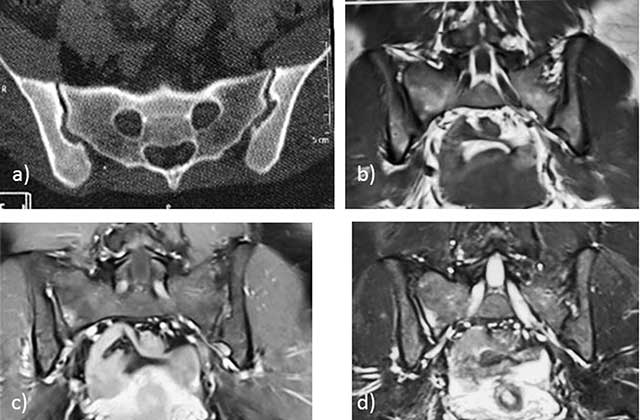

Figure 14

Inflammatory arthritis of the right SI joint of the postpartum in a 27-year-old woman. Axial CT image a) subtle ossifications of the extra-synovial part of the SI joint. T1-weighted b) and STIR c) and d) MR images: low T1 and high T2 signal intensity of the right SI joint cavity with high T1 and STIR signal of the subchondral bone.